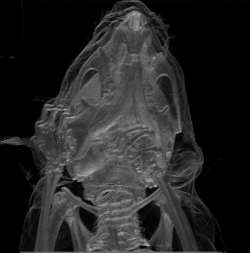

Bosh suyagi, bosh skeleti (lotincha: cranium) – umurtqali hayvonlar va odamning bosh skeleti. Katta yoshdagi kishilarda kalla suyagi choklar bilan birlashgan, chaqaloqlarda bu suyaklar oʻrtasida suyaklanmagan qism – liqildoqlar boʻladi. Odam kallasi 23 suyakdan iborat, ular juft va ayrimlari toq boʻladi. Odamda bosh miya juda rivojlanganligi uchun kalla suyagining miya qismi (kalla suyagi qutisi) katta, yuz qismi pastga choʻzilgan, hayvonlarda esa yuz qismi oldinga choʻzilgan boʻlib, kalla suyagining asosiy qismini tashkil etadi. Kalla suyagi miya va u bilan birga takomil etgan sezgi aʼzolarining tayanchi, ularni tashqi muhit taʼsiridan saqlab turadi. Bulardan tashqari, kalla suyagining yuz qismida organizm hayot faoliyati uchun muhim ahamiyatga ega boʻlgan nafas sistemasining boshlanish qismi – burun boʻshligʻi, ovqat hazm qilish sistemasining boshlanish qismi – ogʻiz boʻshligʻi va eshitish hamda muvozanatni saqlash aʼzolari joylashgan.

Kalla suyagining miya boʻlimi tepa tomondan kalla qopqogʻi bilan chegaralangan boʻlib, ichida bosh miya joylashadigan kalla boʻshligʻidan iborat. Kalla boʻshligʻi umurtqa kanalining kengaygan uchi boʻlib, u yerda bosh miya pardalarga oʻralgan holda joylashgan. Kalla tubidagi teshiklar orqali nervlar (koʻruv, hidlov, uchlik, yuz, eshituv nervlari va b.) va qon tomirlari (uyqu arteriyalari, boʻyinturuq venalari) oʻtadi. Chakka suyagida oʻrta quloq boʻshligʻi va ichki quloq bor. Kalla suyagi ning oʻrtasi asosidagi turk egarida gipofiz yotadi. Ensa suyagida uzunchoq miya joylashgan. Kalla suyagi asosidagi eng katta teshik – ensa teshigi orqali uzunchoq miya orqa miyaga tushadi.

Kalla suyagi gumbazini hosil qiladigan har bir suyak 2 plastinkadan iborat: tashqi plastinkasi qalinroq, ichki (miyaga qaragan) plastinka moʻrt va sinuvchan (buni shishasimon plastinka deb ham ataladi) boʻlib, bosh zarb yeganda (hatto tashqi plastinka shikastlanmaganda ham) sinishi va bunda miya pardasi yirtilib, qon oqishi yoki bosh miyani jarohatlashi mumkin, bu esa hayot uchun xavflidir. Shuning uchun K. s. shikastlanganda uni rentgenda tekshirmasdan, kalla suyagining ichki plastinkasi holatini aniqlamasdan aniq bir xulosaga kelish qiyin. Kalla suyagining 2 plastinkasi oraligʻida yupqa gʻovak modda va vena kanallari mavjud. Kanaldan oʻtgan qon tomir miya boʻshligʻidagi pardalardan hosil boʻlgan vena sinuslarini kallani qoplab turgan teri venalari bilan qoʻshadi. Bu venalar miya boʻshligʻidagi qon oqimini bir meʼyorda saqlaydi. Baʼzan kalla terisi jarohatlanganda zudlik bilan chora koʻrish lozim, aks holda jarohatlangan sohadan qon tomir orqali miyaga mikroblar oʻtib, koʻpgina noxushliklarga olib kelishi mumkin. Kalla suyagining miya qismi – ensa suyagi, peshona suyagi, bir juft tepa suyagi, ponasimon suyak, gʻalvir suyak va bir juft chakka suyaklardan tuzilgan.

Kalla suyagining yuz qismi yuqori jagʻ, bir juft tanglay, yonoq, burun, koʻz yoshi, pastki chigʻanoq, dimogʻ hamda pastki jagʻ va til osti suyaklaridan iborat. Bu suyaklar (pastki jagʻ suyagidan tashqari) bir-biriga oʻzaro chok hosil qilib, pastki jagʻ suyagi esa boʻgʻim orqali birikadi.